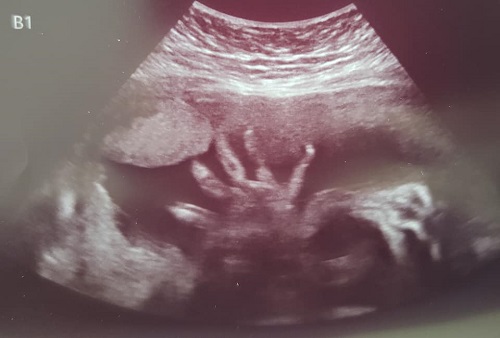

When the finally called us back, I took my seat in the chair across from Sam. She got up on the table and the tech went through the standard questions and such. She finally put the gel on the wand and began to search for the baby. I sat on the edge of my chair as I watched for his image to appear. I could see he was moving around a bit. One of the first things we saw was his hand. It looked like he was waving to us.

They did a lot of measuring today. This will supposedly will tell you what the baby weighs. As the tech continued to move the wand around, I saw him holding his foot. He is breech, which means his head is up instead of down. Ella was this way around the same time, but she turned, which is what we are hoping he will do.